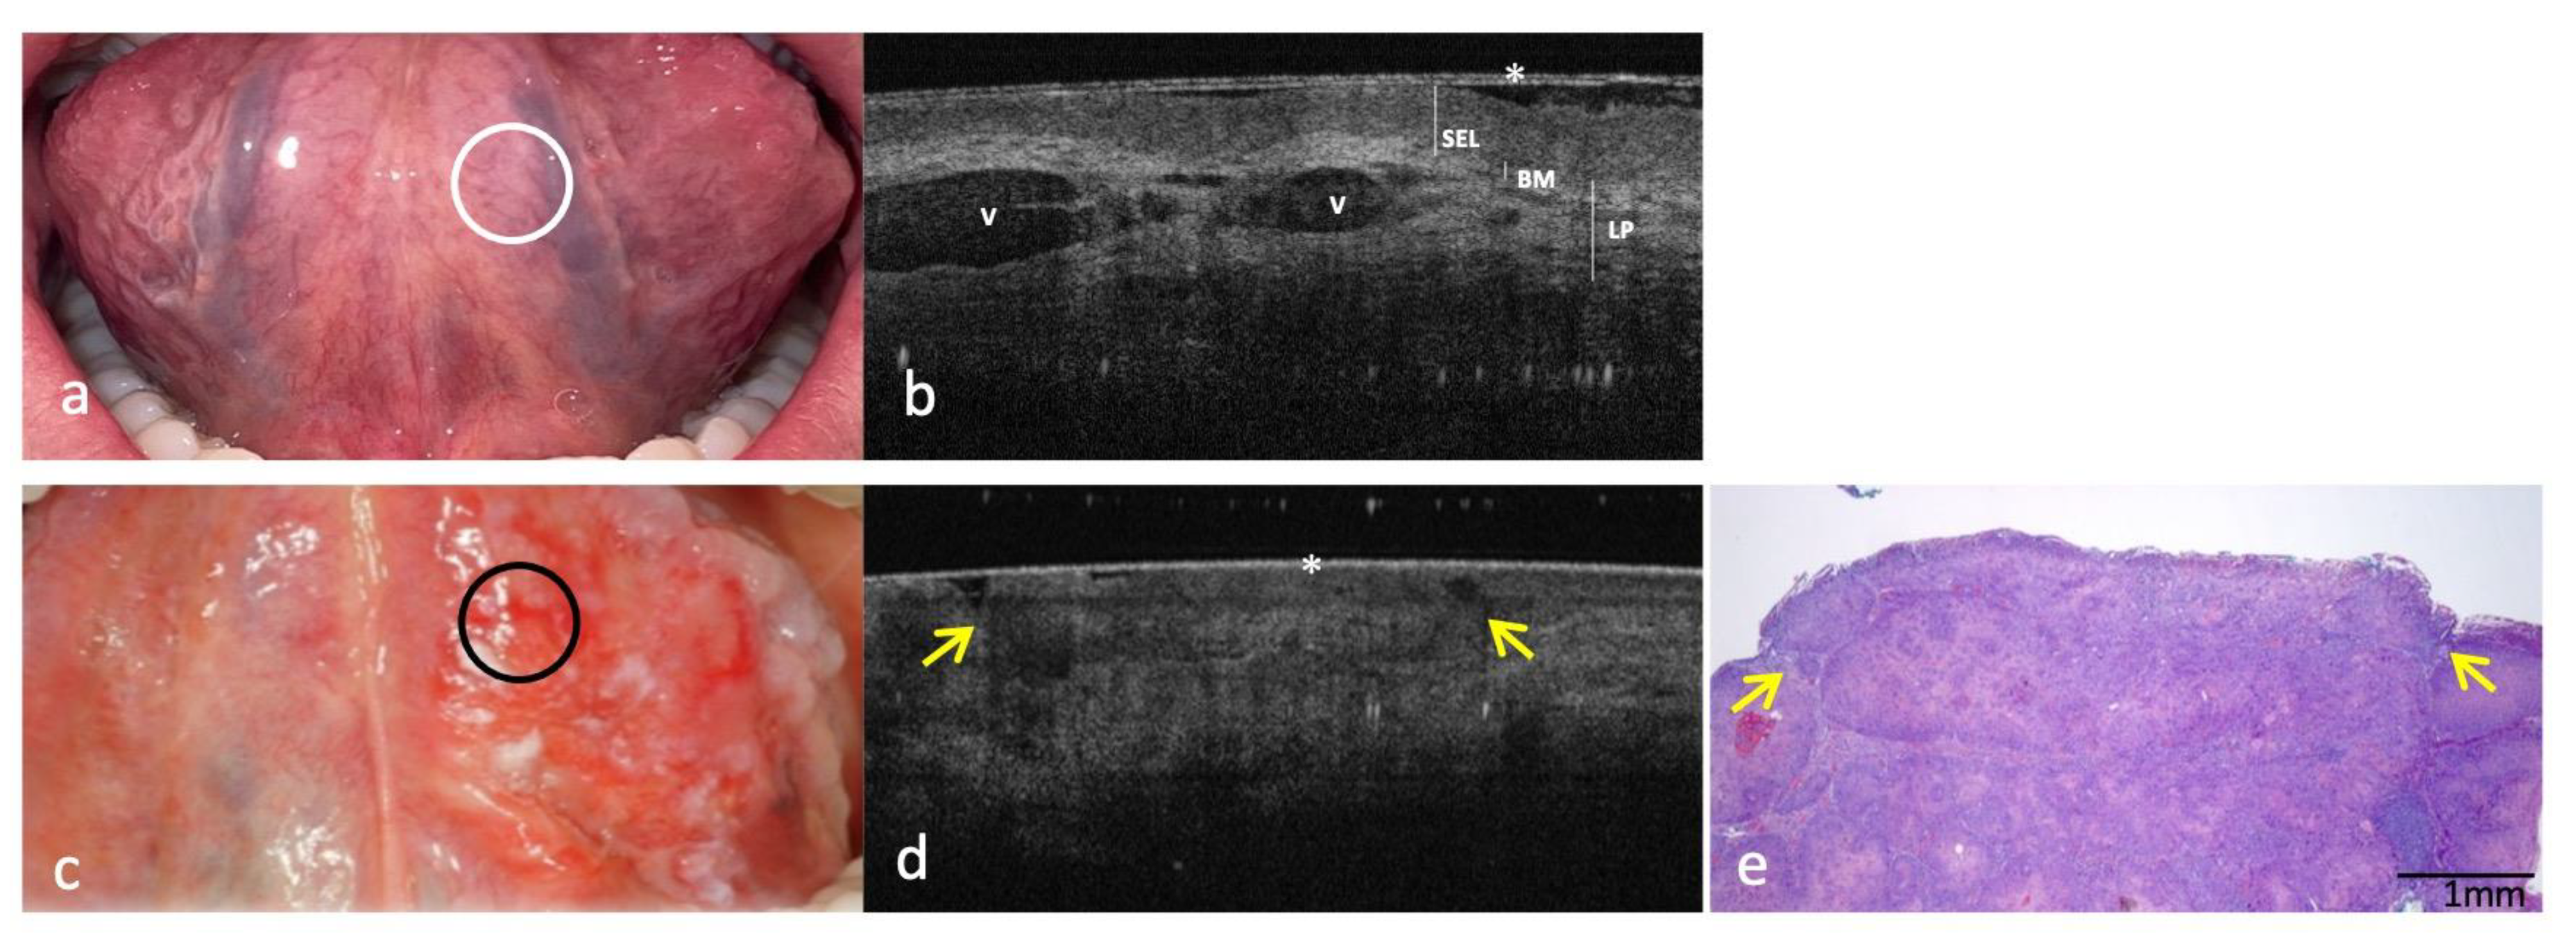

3.4. Clinical, OCT and Histopathology of OSCC on Low Anterior Alveolar Mucosa and Mandibular Gingiva Compared to the Same-Site Healthy Mucosa (Site Code C03.1)

| Ventral surface of tongue (site code C02.2) | ||

| KL | Physiologically not present | Not present |

| SEL | Assessable/Hypo-reflective | Not assessable |

| BM | Continuously assessable | Not assessable |

| LP | Well demarcated/Distinguishable from SEL Hyper-reflective and lax reticular structure surrounding blood vessels | Not demarcated/Indistinguishable from SEL |